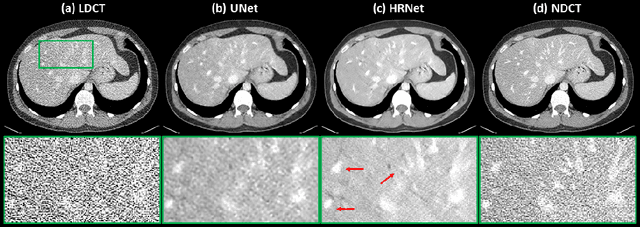

Abstract:Low Dose Computed Tomography (LDCT) is clinically desirable due to the reduced radiation to patients. However, the quality of LDCT images is often sub-optimal because of the inevitable strong quantum noise. Inspired by their unprecedent success in computer vision, deep learning (DL)-based techniques have been used for LDCT denoising. Despite the promising noise removal ability of DL models, people have observed that the resolution of the DL-denoised images is compromised, decreasing their clinical value. Aiming at relieving this problem, in this work, we developed a more effective denoiser by introducing a high-resolution network (HRNet). Since HRNet consists of multiple branches of subnetworks to extract multiscale features which are later fused together, the quality of the generated features can be substantially enhanced, leading to improved denoising performance. Experimental results demonstrated that the introduced HRNet-based denoiser outperforms the benchmarked UNet-based denoiser in terms of superior image resolution preservation ability while comparable, if not better, noise suppression ability. Quantitative metrics in terms of root-mean-squared-errors (RMSE)/structure similarity index (SSIM) showed that the HRNet-based denoiser can improve the values from 113.80/0.550 (LDCT) to 55.24/0.745 (HRNet), in comparison to 59.87/0.712 for the UNet-based denoiser.